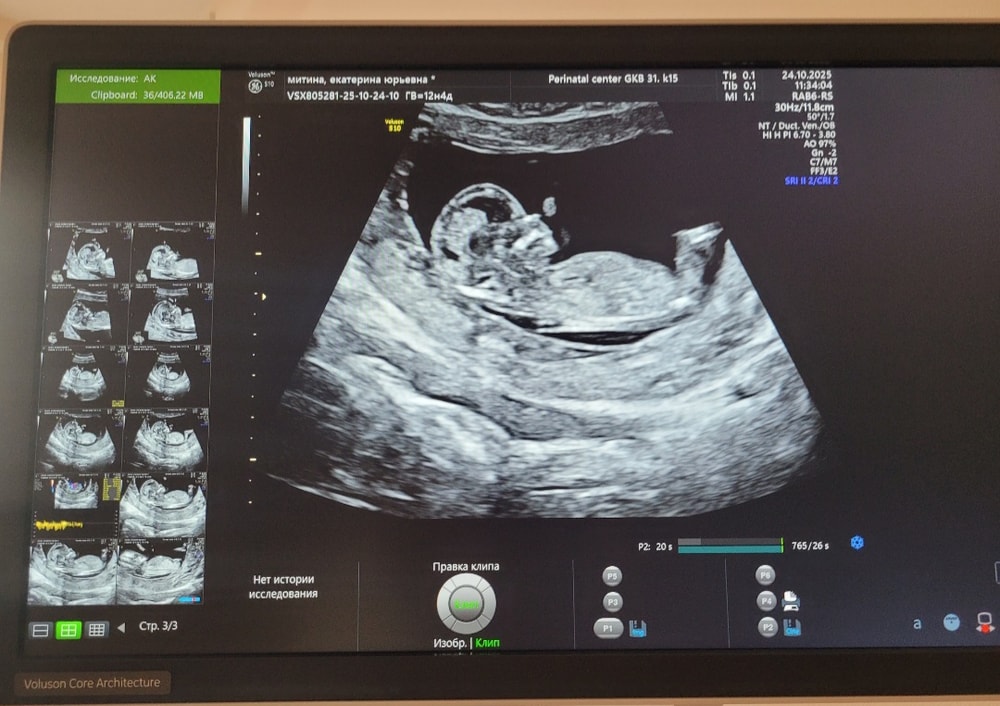

Никогда еще за 3 беременности (2015, 2018 и 2021 г.) мне не говорили пол на первом скрининге. Но сейчас я впервые делала его в новом перинатальном центре. Аппаратура явно отличается от аппаратов в обычных женских консультациях. Врач сказала, что пол неплохо так определяется.

Срок 13 недель.

Это суперский аппарат voluson e10 , экспертный , поэтому и увидели ☺️ мне дочку тоже на этом аппарате в 1 скрининг разглядели ❤️